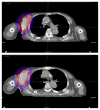

Brachytherapy (BT) is an important local treatment of tumor and it can be applied to different anatomical sites either in a curative or palliative setting. BT can deliver large dose of radiation to the tumor while sparing the surrounding normal tissue which translates into a better therapeutic ratio compared to external beam radiotherapy. However, the evidence for the use of brachytherapy in the palliative setting is lacking in the literature. In this case report, we describe the brachytherapy technique and outcome of a patient with squamous cell carcinoma of the hypopharynx who underwent palliative brachytherapy to the hypopharynx and metastatic tumor at the right axilla.